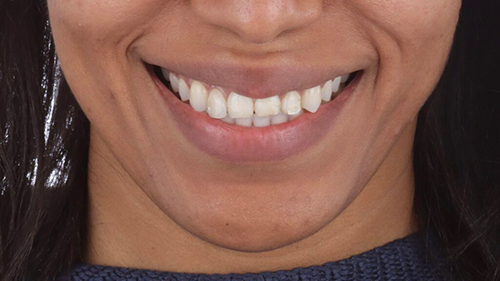

Initial situation